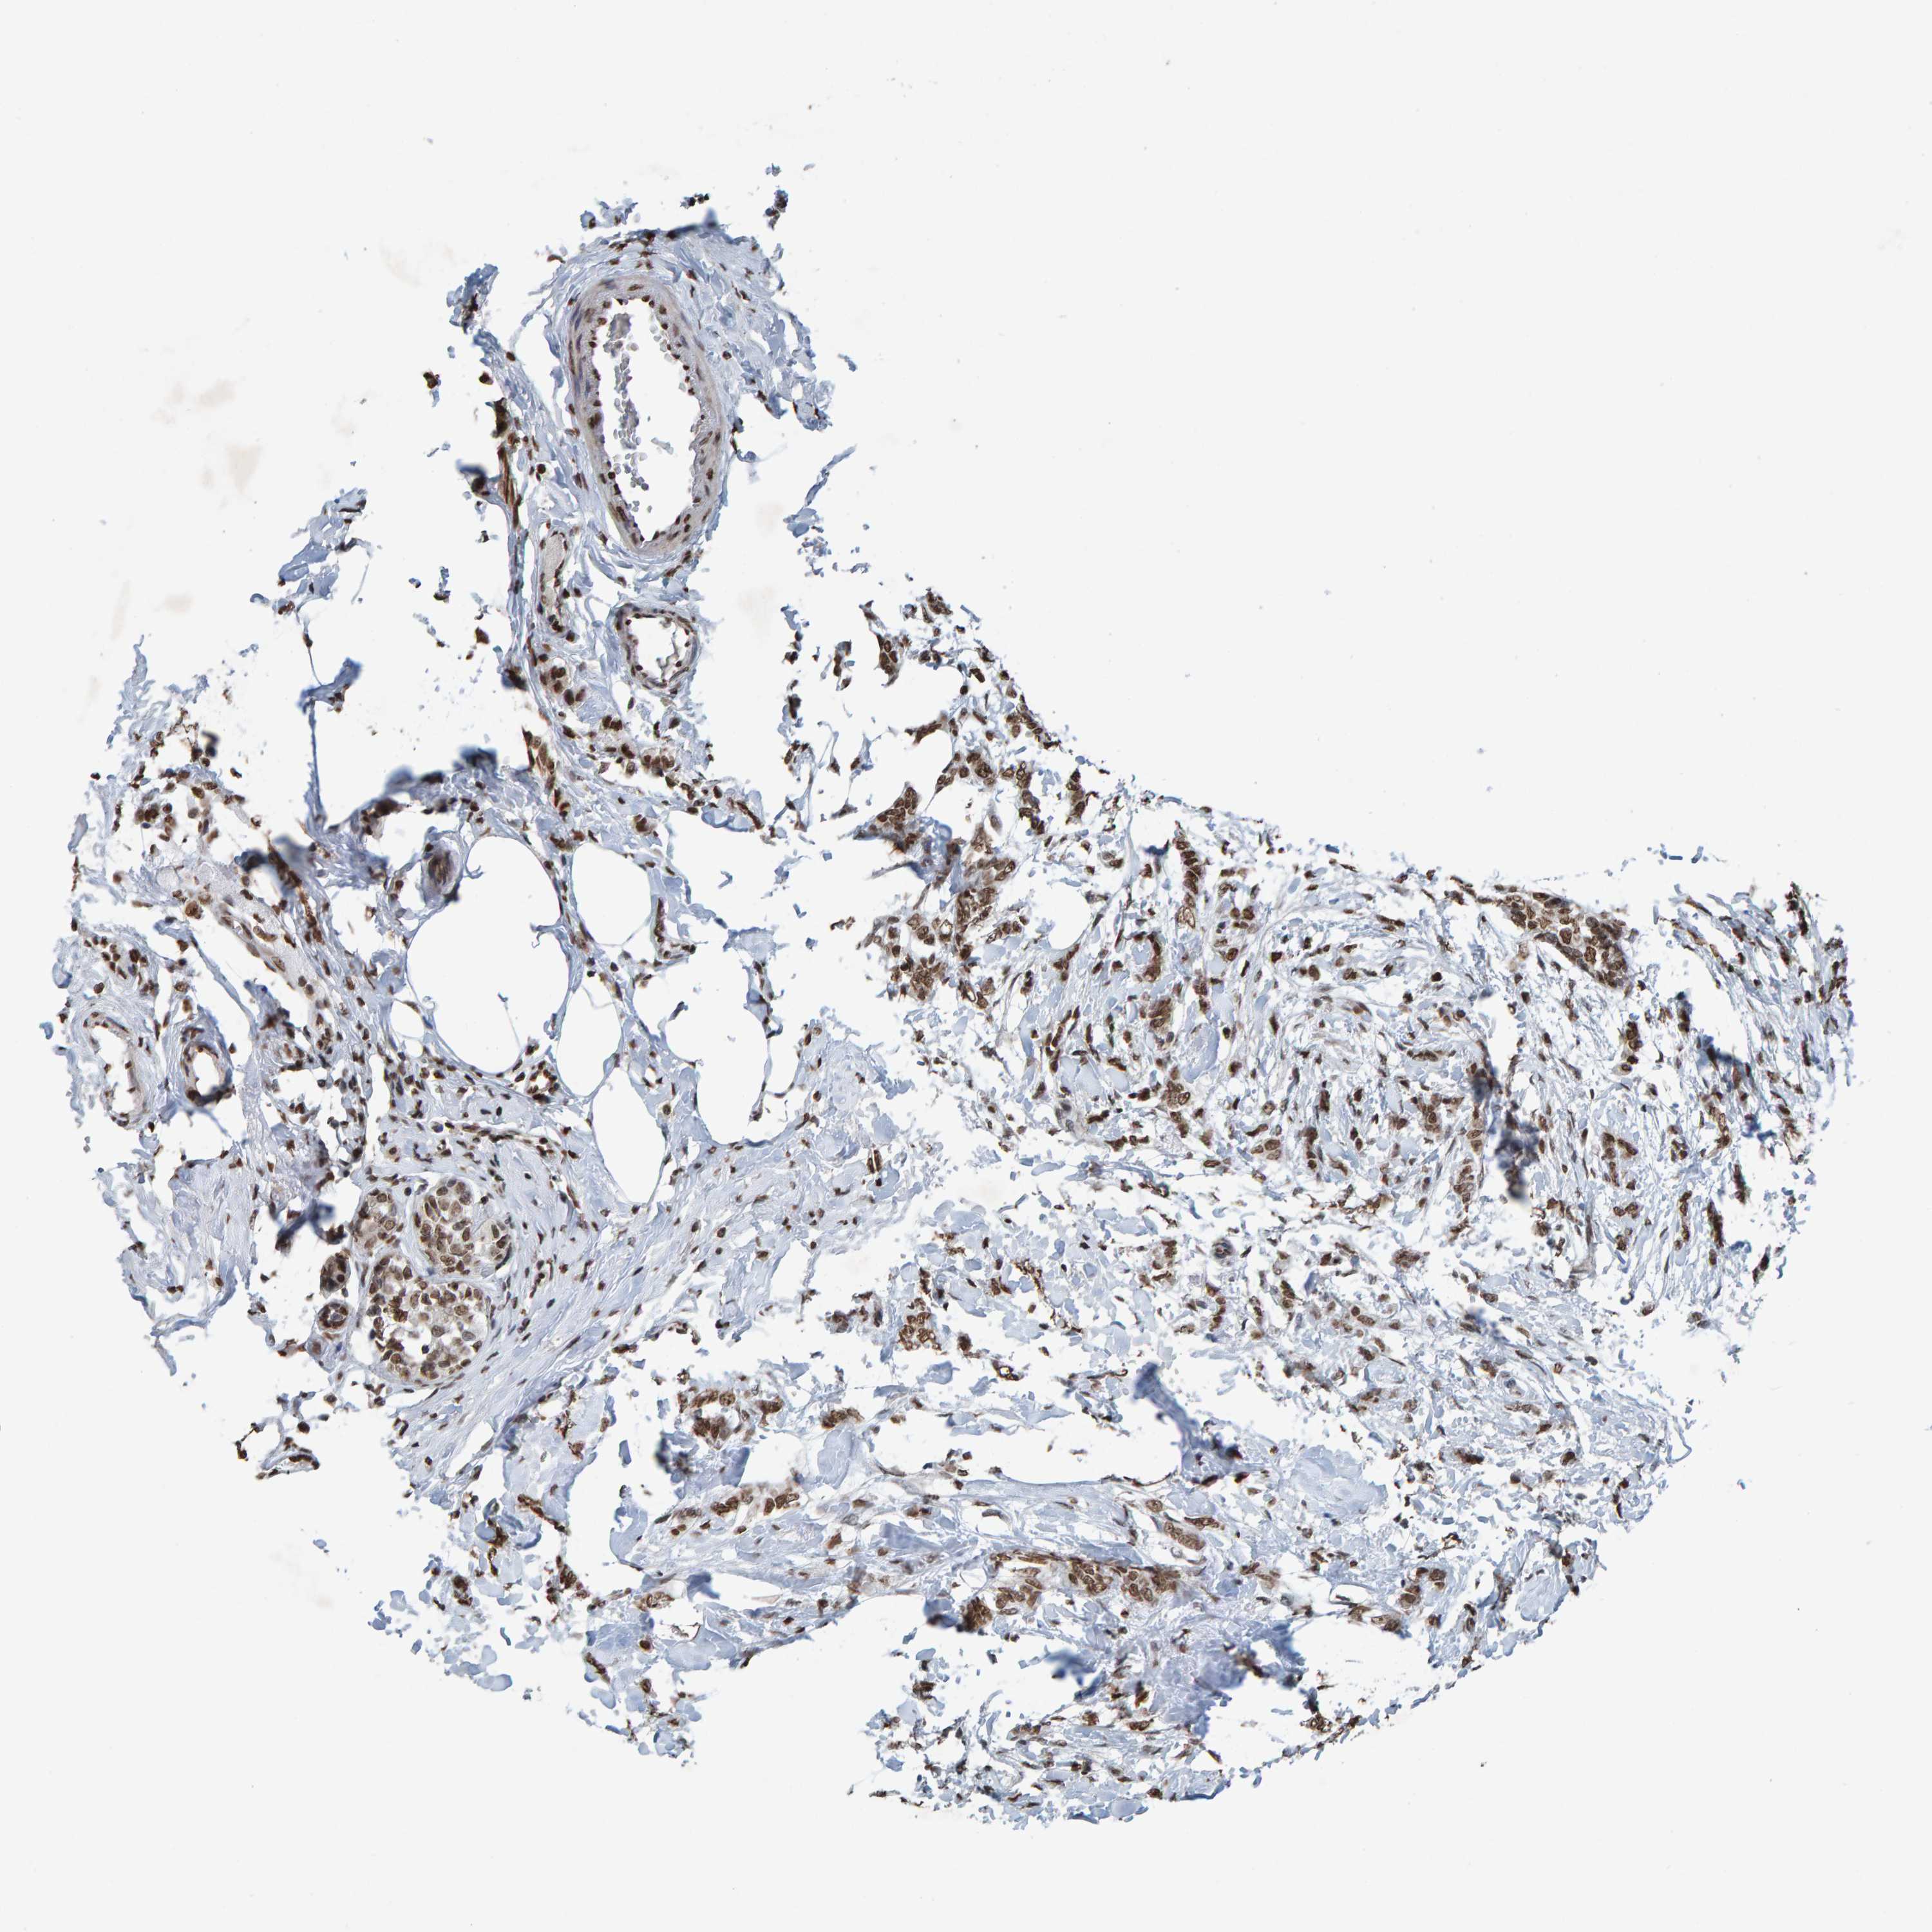

CANCER BREAST CANCER Show tissue menu

BRCA TCGA BRCA VALIDATION PROTEIN EXPRESSION